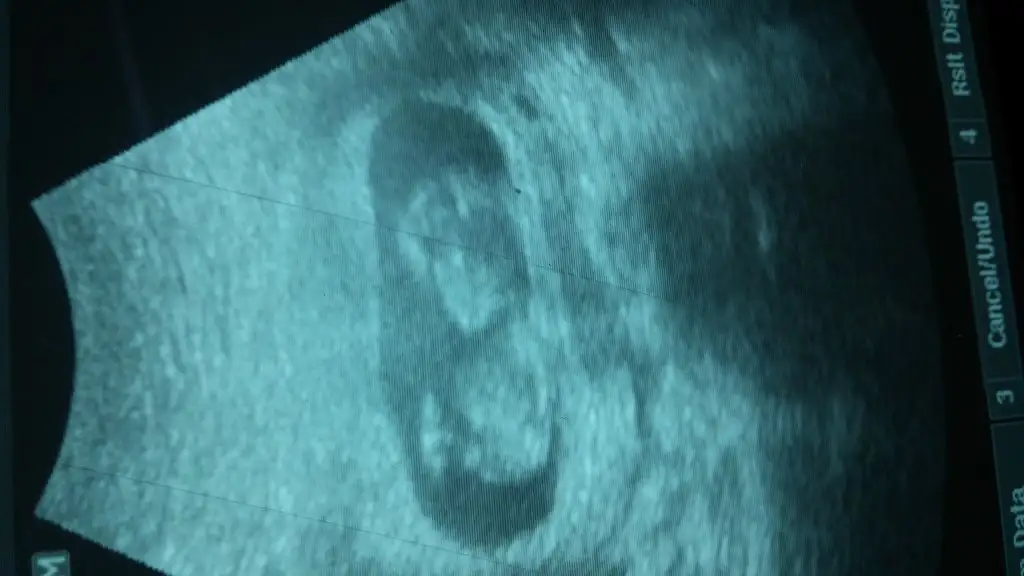

Sanki kiza benzettim benMerhaba, bugün randevumuz vardı ..goruntumuz aşağıda..10+1 haftalığız.. Belli oluyormu sizce, nedir cinsiyetimiz

erkek....Bi tahmnde bna yapablrmsnz :)

erkek...Kızlar gecen haftada paylaşmıştım karışık yorumlar geldi. Bu da bı haftaki. Yorum![]()